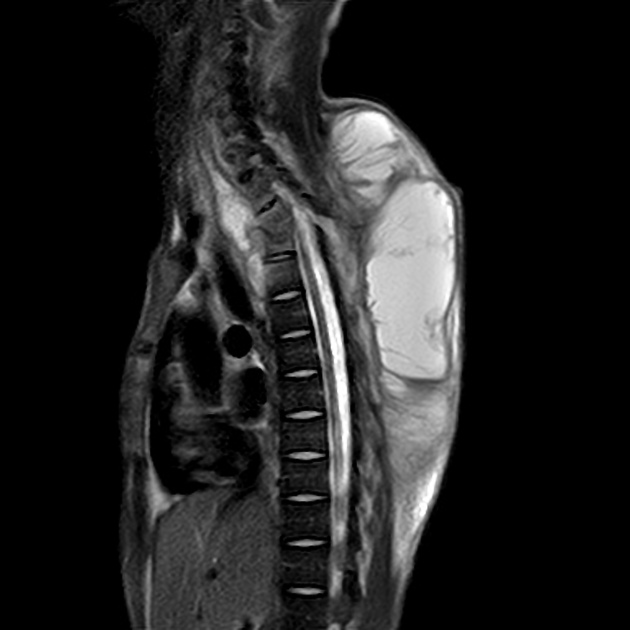

Tüberküloz spondilitin sık görülen bir komplikasyonu olarak karşımıza çıkar.

Kemiğe kan yolu ile ulaşan tüberküloz basili yüksek 02 konsantrasyonu istediğinden başlangıç enfeksiyonu sıklıkla sinovyadadır. Ardından infeksiyon komşu epifize yayılır ve tipik granülomatöz reaksiyon, kazeöz nekroz ve yaygın kemik yıkımını burada oluşturur. En sık vertebra tutulur (Pott hastalığı) (Vertebranın korpusunun anteriorunu tutar).

Vertebral deformite ve kollapslara; sekonder nörolojik defisitlere neden olur. Tbc osteomyelitinin komşu yumuşak dokulara ilerlemesi özellikle psoas kasları arasında soğuk abselere (pott absesi) neden olur.(Abse vardır ama bulguları yoktur)